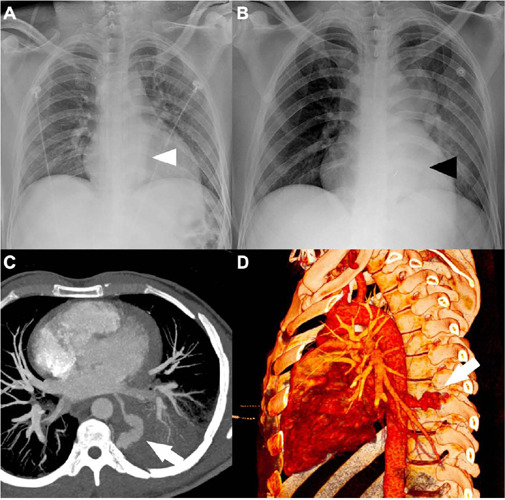

Abstract Image